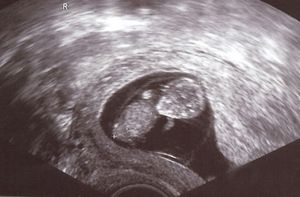

Sie sind hier: Startseite Nachrichten Gesundheit Sauerstoffmangel: Kinder früher unfruchtbar Im Mutterleib: Sauerstoffmangel hat gravierende Folgen.

Im Mutterleib: Sauerstoffmangel hat gravierende Folgen.